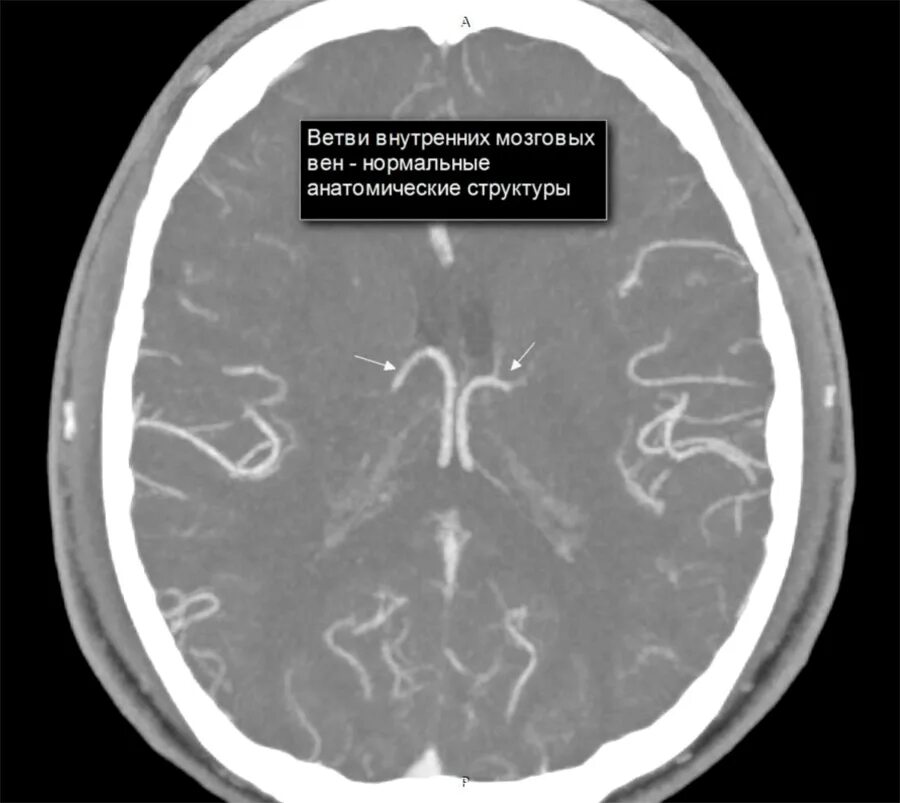

Диффузные изменения срединных структур головного мозга